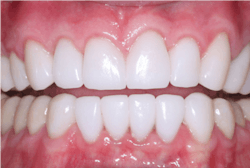

- Lithium disilicate (IPS e.max): Well-proven material, except for bruxers; consider using for single crowns (figure 3)